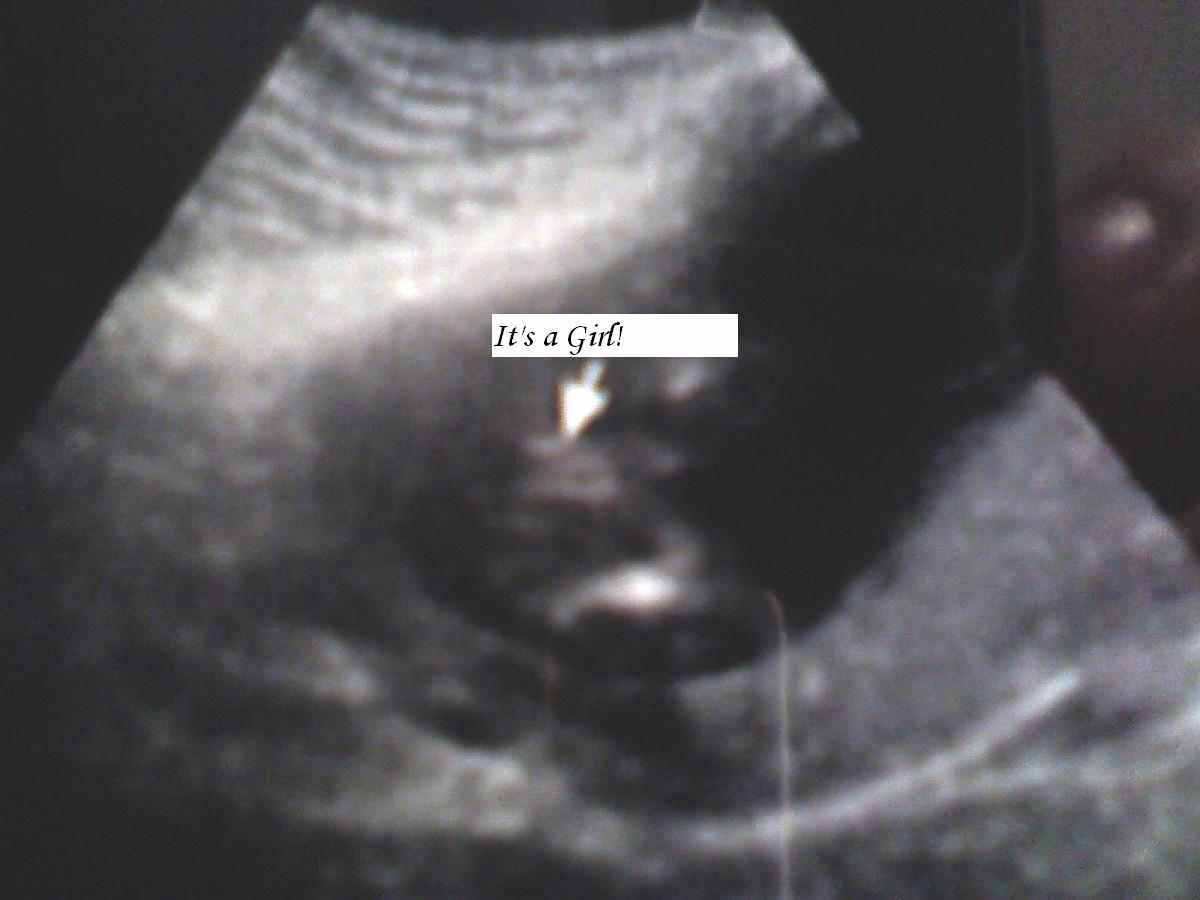

Hello I want to share my potty girl shot. Hope it helps :) Attachment 18993

Sent from my SPH-L900 using Tapatalk

I really hope this is your boy! I do not see three lines in yours so Im keeping my fingers crossed for you 😁